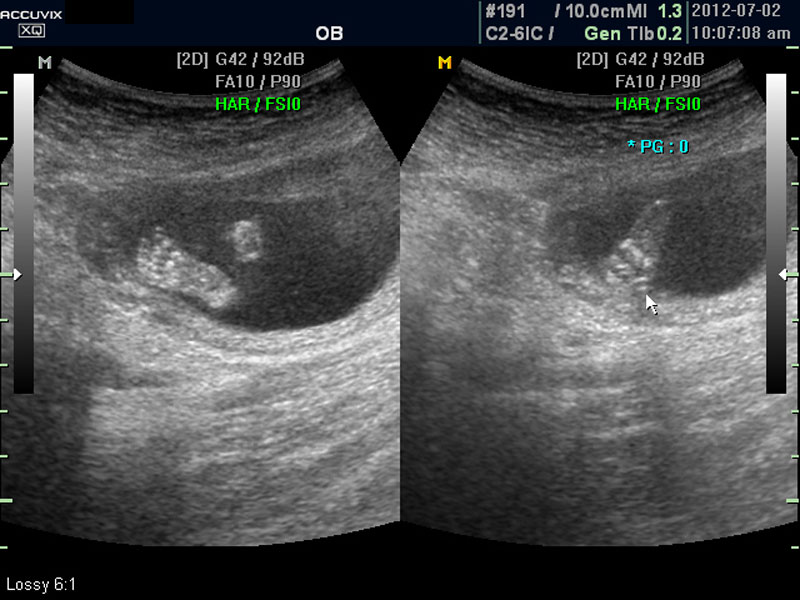

임신 중기의 초음파에서는 아기의 크기, 심장 박동이나 활동의 정도, 각종 장기의 구성이 정상인가 하는 것을 살펴 보게 됩니다.

태아의 대부분 장기는 임신 중기에는 이미 다 형성이 되고 이때부터는 크기가 커지면서 기능이 갖추어지는 시기입니다.

따라서 가장 여러가지 소견을 자세히 살펴 보아야 하는 시기에 해당하며 기형아 검사라고 하는 혈액 검사나 양수 검사도 보통 이 시기에 하게 됩니다.

우선 초음파 사진에서 볼 것은 태아의 크기가 정상인가 하는 것입니다.

화면에서는 위쪽에 하얗게 균일하게 보이는 것이 태반의 모습입니다.

태반은 실제로 보면 피자처럼 둥그런 원판 모양이며 임신 후기로 갈수록 태아와 마찬가지로 크기가 커지고 두꺼워집니다.

양수의 양은 태아의 건강과 관련된 지표로 너무 많거나 너무 적으면 좋지 않은데 그 절대양을 측정할 수는 없어서 양수가 많은 부분의 깊이를 측정하거나 혹은 개략적으로 전체에서 차지하는 부분을 봐서 이상 여부를 판단합니다.

사진에서 검게 보이는 것이 양수입니다. 양수에 대하여는 색깔이나 밀도 등 다른 요소는 알기 어려워서 그 양만 가지고 판단을 하게 됩니다.